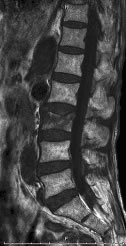

UAE前MRI

子宮内に大小多数の筋腫核が存在しています。手術的治療では子宮全摘術しかありません。

UAE 1ヵ月後造影MRI

塞栓術により殆どの筋腫核が壊死し、造影効果がなくなっています。半年から1年をかけて吸収されます。